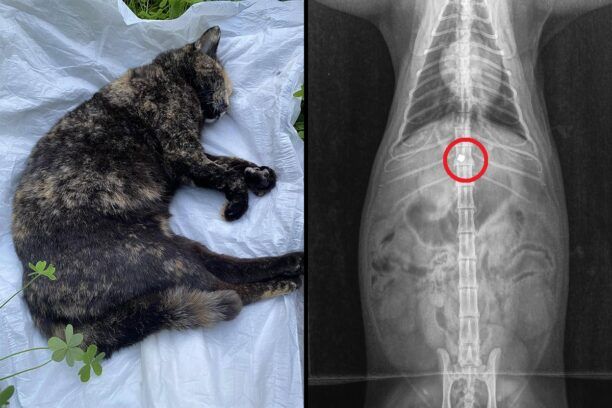

Μια γάτα παράλυτη πυροβολημένη στην σπονδυλική στήλη με αεροβόλο εντοπίστηκε στον Πύργο Ηλείας. Το ζώο βρέθηκε ζωντανό στα Λαστέικα περίπου απέναντι από το συνεργείο αυτοκινητών «ALFA CAR» από τον άνθρωπο που το φρόντιζε μέσα σε ένα χαντάκι. Aρχικά νόμιζε ότι το χτύπησε αυτοκίνητο...

«Σήμερα πήγα να βοηθήσω ένα φίλο μου να πιάσουμε την αδέσποτη γατούλα που φροντίζει εδώ και χρόνια … ήταν μέσα σε μια γράνα και έσερνε τα πίσω ποδιά της …

Την πήγα αμέσως στον κτηνίατρο , της έκανε ακτινογραφία και εκεί είδαμε το αδιανόητο για ακόμα μια φορά …

Η γατούλα είχε δεχτεί βόλι από αεροβόλο ή αλλιώς ΦΛΟΜΠΕΡ ….

Το νου σας μη σας πετύχει κι εσάς , έχει πολύ καλό σημάδι όπως βλέπετε!